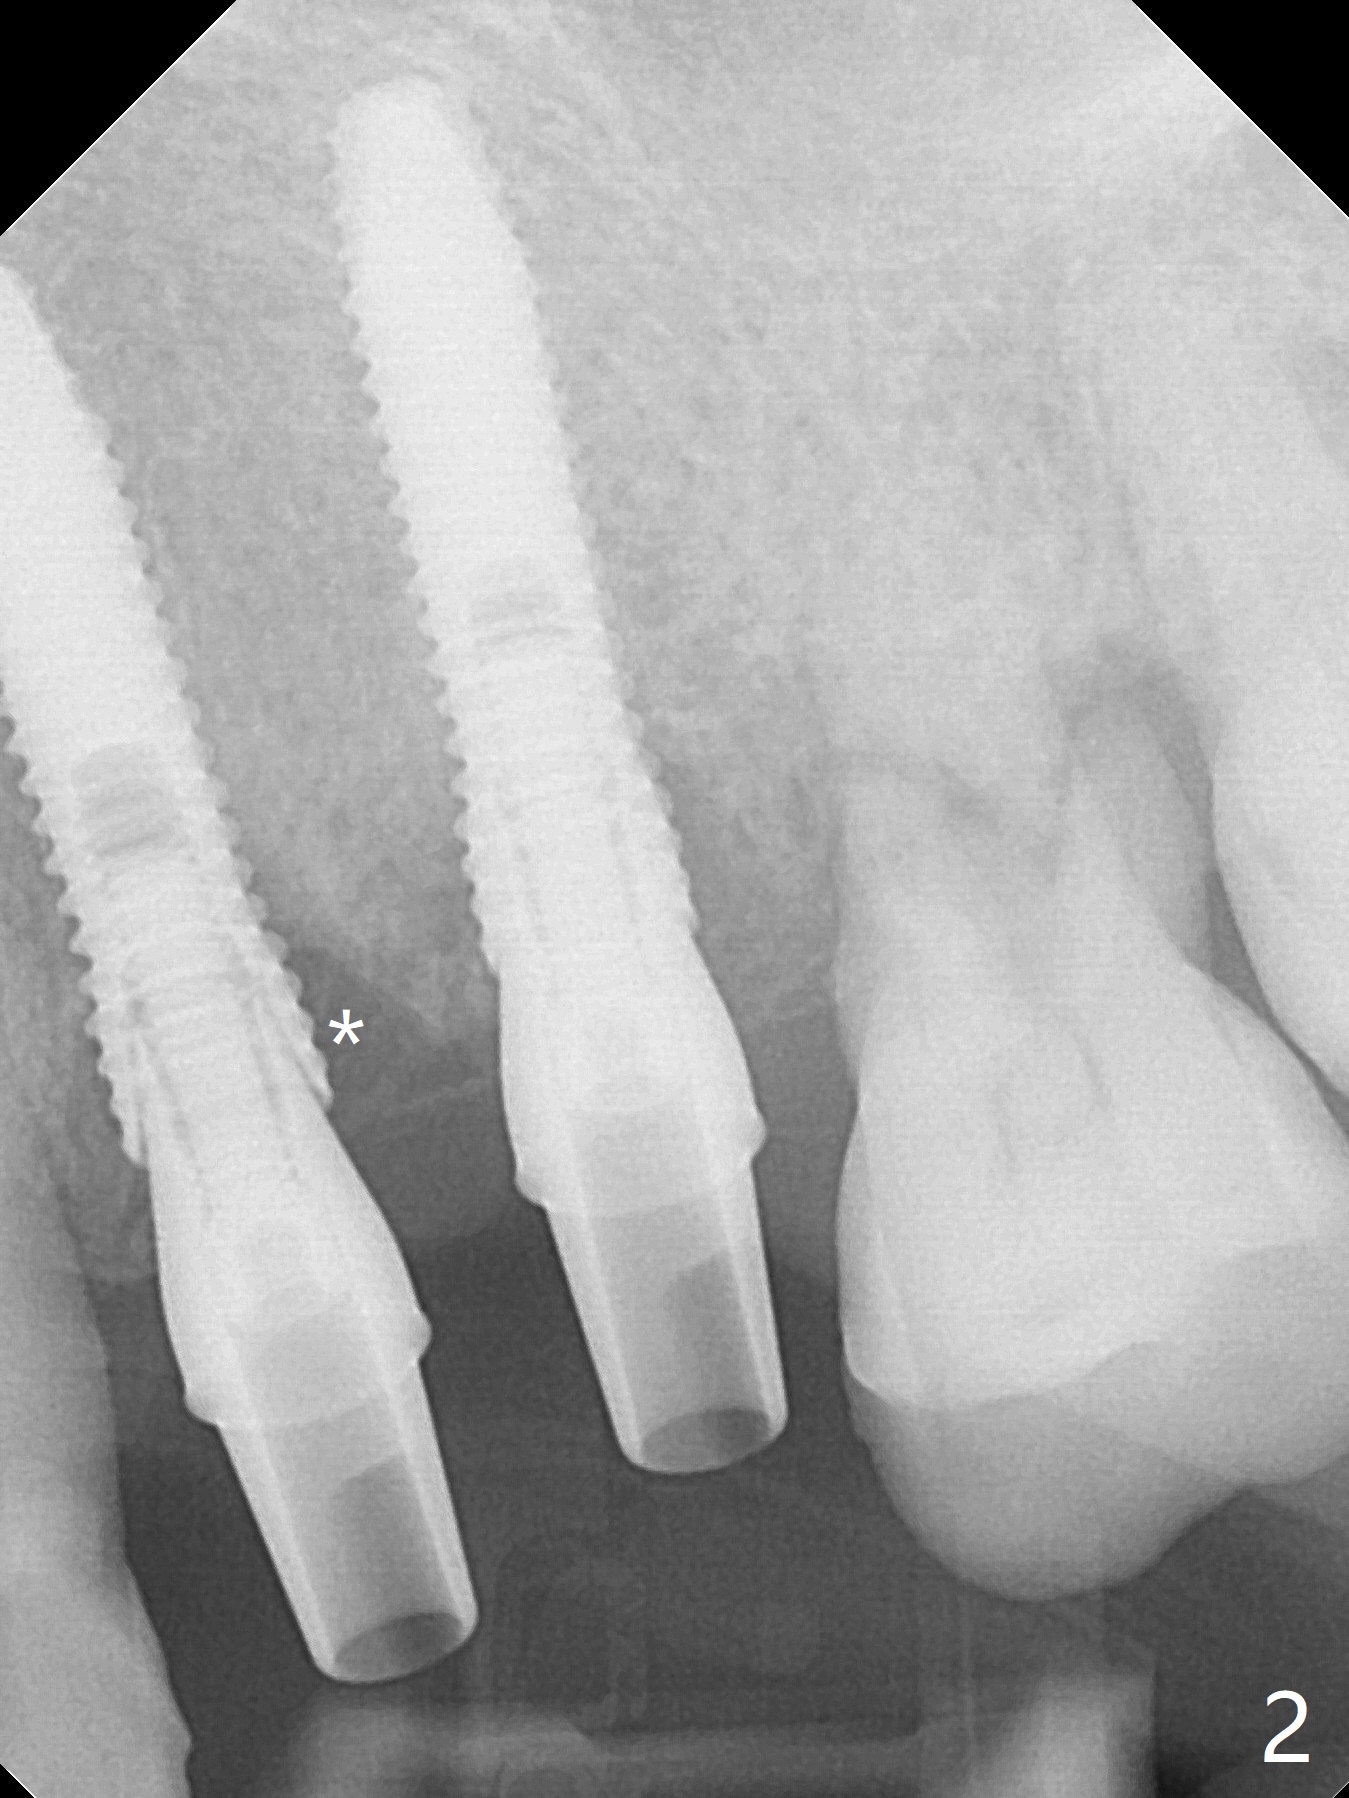

A 66-year-old woman returns to office requesting implant placement at #12 and 13 at an appointment supposed for #5 impression. Depth of osteotomy is 20 mm (gingival level, Fig.1 ( 2mm)). After correction of trajectory at #12 and 3 mm drill for 16 mm at the sites, two of 3.8x16 mm implant are placed with insertion torques of 35 and 15 Ncm, respectively (Fig.2). Before and after change into shorter abutments (4.5x4(4) and (5)), Vera Graft is placed (Fig.3 *). To increase stability, either increase the diameter (4 (Fig.4 at #5) or 4.5 mm instead of 3.8) or length of the implants (red dashed line: sinus floor). Or use dummy implants. The allograft appears to have been incorporated into the host bone nearly 4 months postop (Fig.5). The abutment of the isolate implant at #5 becomes loose twice (Fig.4). To reduce the chance of abutment loosening at #12 and 13, can you make splinted crowns? If the two separate crowns have been fabricated, can you make a slot (with light undercut) in the proximal area of each crown (Fig.6 (occlusal view): S) in addition to access hole (A)? After cementation, composite will be placed in the slots (lock) so that the crowns will not rotate and become loose.